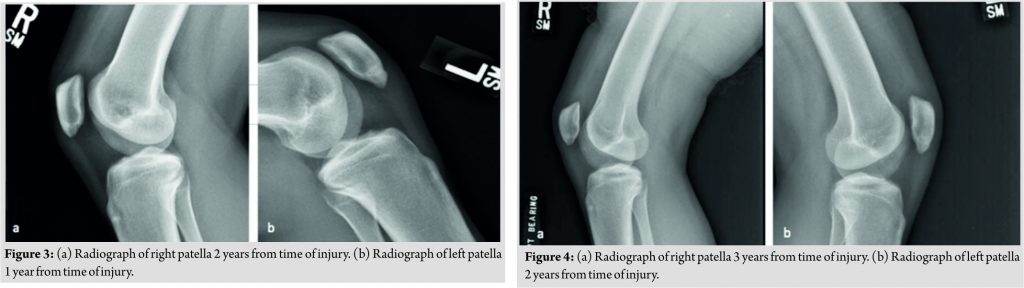

An MRI was obtained that confirmed the diagnosis of a patellar stress fracture and ruled out any patella tendon or intra-articular pathology (Fig. 1). The patient was immobilized in a hinged knee brace, locked in extension. She was also prescribed Vitamin D and calcium supplementation as well as daily use of an Exogen® LIPUS system(Bioventus LLC, Durham, NC, USA). It was discussed with the patient that since the injury was 2–3 months’ old, she was at a higher risk for failing conservative treatment, which would require operative fixation. At 1month follow-up, radiographs were obtained that showed early callus formation, and her examination revealed a clinical decrease in her pain. She was then progressed to weight bearing as tolerated with gradual increase in her range of motion guided by physical therapy. At 2 months, radiographs showed fracture healing, and we began gradual reintegration of gymnastics with limitations on tumbling/dismounting/jumping activities. At 3 months, she was allowed to return to full competition. After approximately 1year of returning to sport and competing as a collegiate gymnast, she unfortunately began to develop similar symptoms as before, now in her contralateral knee. She presented back to our office where we confirmed the diagnosis of a stress fracture of the inferior pole of the contralateral patella, similar to her previous injury (Fig. 2). At that visit, radiographs revealed complete healing of her prior stress fracture from 1year ago. She was given the same conservative management plan of a period of immobilization in a hinged knee brace locked in extension, Vitamin D and Calcium supplementation, daily use of LIPUS, and later progressed to physical therapy with guided return to gymnastic activities. At 3 months, she was pain free, and a Knee Injury and Osteoarthritis Outcome Score (KOOS) survey was obtained [Graph1][20]. With the KOOS showing favorable results, in addition to being pain free, the patient was allowed a full return to competition(Fig. 3). She is now 3 years from injury on the right knee and 2years from injury on the left knee and continues to compete at the Division I collegiate level without pain(Fig. 4).